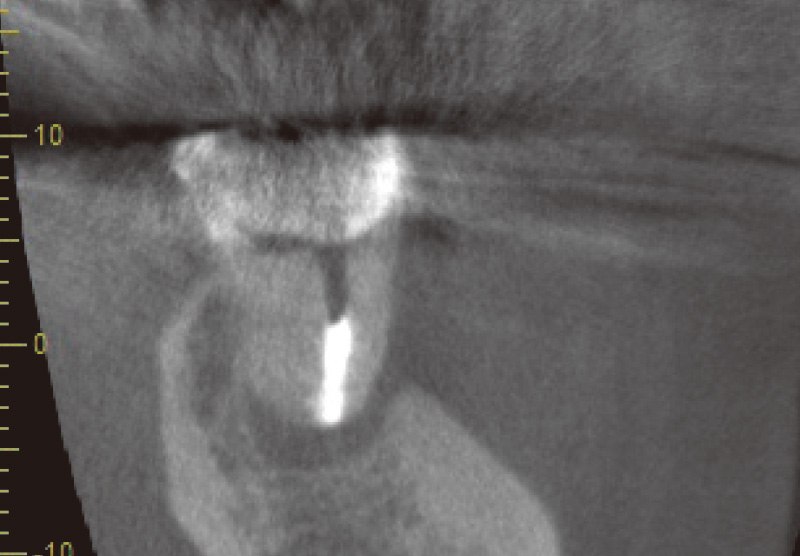

症例紹介② 根尖が開大した難治性根尖性歯周炎 菅谷 勉先生

![[写真] CT](/academic/dentalmagazine/wp-content/uploads/sites/2/2025/11/195-3_photo08.jpg)

CTで見ると、近心頰側根も遠心頰側根にも根尖部病変があり、口蓋根は吸収していて、根尖孔が拡大している。この状態になると、根管洗浄を行っても十分細菌が取り切れず、治癒が難しくなる。(Veraviewepocs 3Dfにて撮影) -